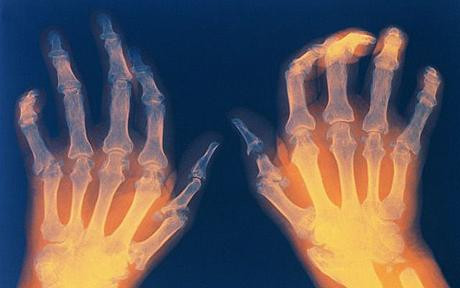

Viêm khớp dạng thấp: Viêm khớp dạng thấp có xác suất xảy ra ở cả nam và nữ ở độ tuổi 20. Không có cách chữa bệnh này nhưng các loại thuốc chống viêm và steroid có thể giúp giảm nhẹ bệnh.